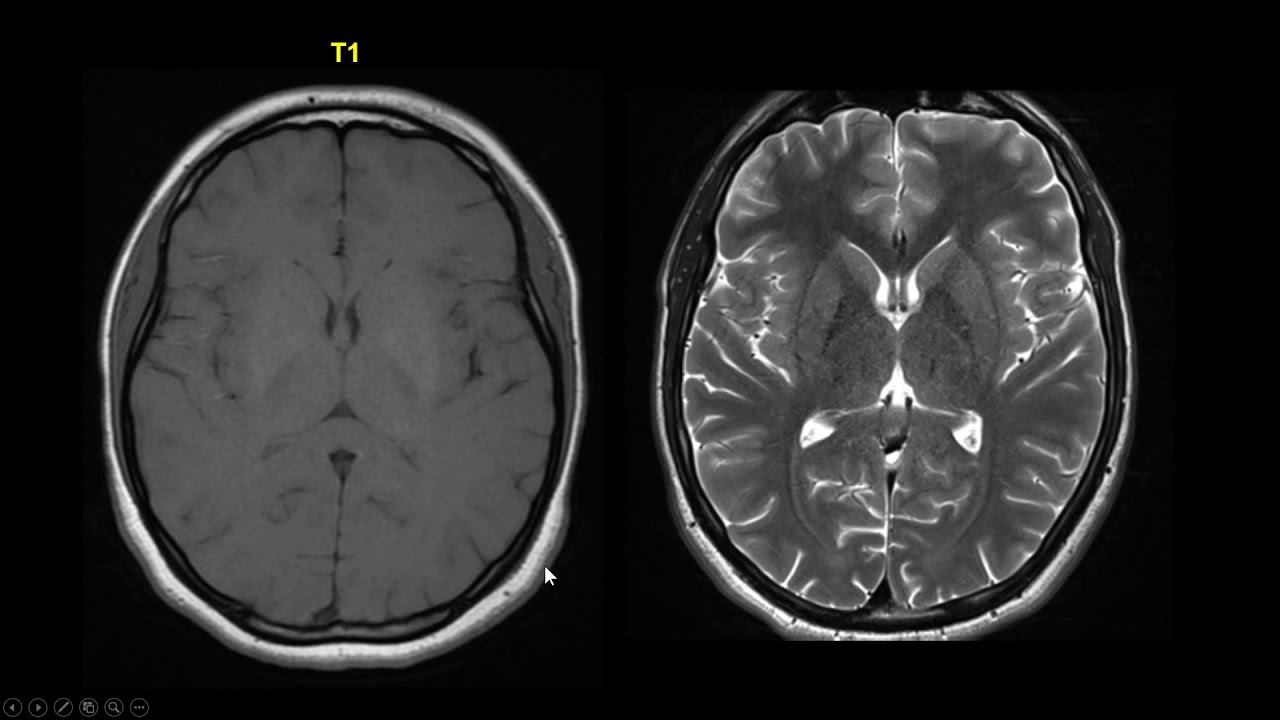

que vocês querem de um próximo conteúdo Então a gente vai tentar aqui eh simplificar da melhor forma possível Eh esses esse exame que na vista de muitas pessoas é um pouco complexo A princípio eu gostaria de fazer uma diferença entre a ressonância magnética e a tomografia que eu vejo que há Muita confusão às vezes principalmente para quem tá iniciando quem tá vindo do zero ali e confunde um com o outro por causa dos equipamentos serem parecidos então eu vou colocar aqui uma imagem aqui ó do lado para vocês verem aqui a gente tem o equipamento

primeiro de tomografia computadorizada e o equipamento de ressonância e o que eu quero que vocês observem é que o equipamento na parte física dele ali eh do de tomografia computadorizada a gente vai ter um um aparelho um pouco pouco mais pequeno é o tubo dele não é tão profundo quanto de ressonância magnética na ressonância a gente vai ter um aparelho mais robusto maior e com algumas características um pouco diferentes então só no visual Eles são diferentes mas a grande diferença entre tomografia e ressonância são os princípios de formação da imagem eh a ressonância magnética irá

utilizar o magnetismo e bobinas de radiofrequência que a gente vai abordar enquanto a tomografia computadorizada Ela utiliza os raios X para produzir a imagem Então são princípios físicos totalmente diferentes de um para o outro algumas coisas na imagem pare um com outro mas são totalmente diferentes Então vamos agora já falar sobre o equipamento de ressonância abranger a parte interna desse equipamento de ressonância eu vou mostrar aqui para vocês essa imagem que está aqui do lado onde a gente consegue observar o o gendre ali o o o aparelho de ressonância aberto e a gente vê algumas